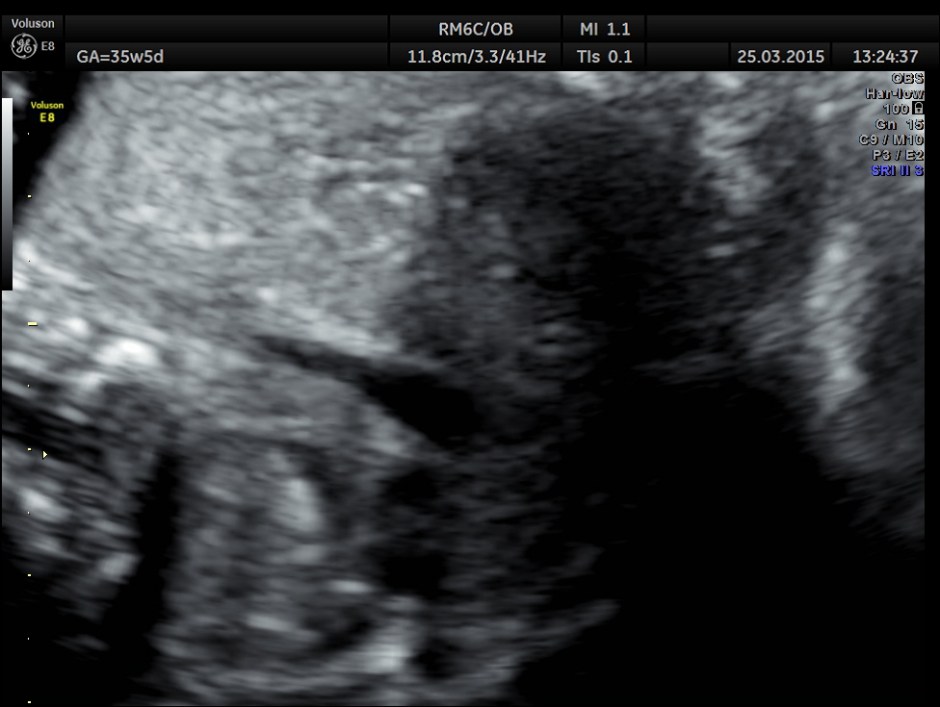

Cardiomegaly with dilated left ventricle and small right ventricle were obvious.

This is a 3 D image showing similar findings. Both pictures also show the pulmonary veins draining into left atrium and the left atrium opening into left ventricle and the right atrium opening into right ventricle. ( free wall attachment of the mitral valve leaflet,moderator band seen in the right ventricle and the tricuspid shows a septal leaflet.)

The 4 chamber view showed LV to be dilated.